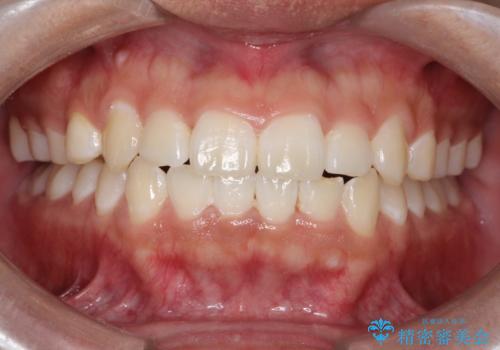

[インビザライン ライト] 短期間(3.5ヶ月)で終わるマウスピース矯正

![[インビザライン ライト] 短期間(3.5ヶ月)で終わるマウスピース矯正の症例 治療後](https://seimitsushinbi.jp/wp/wp-content/uploads/2020/02/2f36cdf472a802b537022ae239b8cb6b-500x350.jpg?v=1580813669)